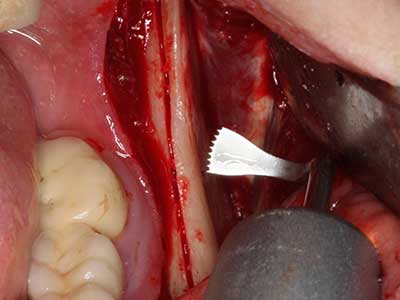

Sollen chirurgische Eingriffe mit unmittelbarer Knochenbeziehung an empfindlichen Strukturen wie Blutgefäßen oder Nerven erfolgen, so bergen rotierende Instrumente ein erhebliches Potential an iatrogener Schädigung. Gerade bei Nervdarstellungen nach iatrogener Schädigung, oder aber im Zuge einer Nervlateralisation für resektive und rekonstruktive Eingriffe oder Implantatinsertionen können piezoelektronische Geräte hilfreich sein Knochendeckel zu präparieren und nervnahe Hartgewebsanteile zu entfernen (Abb. 17-20). Ein leichter Kontakt des Nervstrangs zur Piezospitze bleibt dabei in der Regel folgenlos – allerdings kann eine unvorsichtige Vorgehensweise mit sägeartigen Bewegungen bzw. Ansätzen bei noch vorhandener knöcherner Unterlage durchaus temporäre oder aber auch permanente Nervschädigungen verursachen. Das Risiko einer solchen Schädigung wird jedoch als wesentliche geringer eingeschätzt als unter Anwendung von Säge- oder Fräsinstrumenten (Pereira, Gealh et al. 2014).

Bei der Knochenblockentnahme zeigen sich weitere Vorteile für die Piezochirurgie: Neben der bereits beschriebenen hohen Präzision bei der Osteotomie stellt sich gerade die Verwendung der dünnen Sägespitzen als besonders materialschonend heraus. Bei der Verwendung insbesondere von Lindemannfräsen sind mit deutlich höheren Entnahmeverlusten durch die dickere Instrumentenspitze zu rechnen (Lakshmiganthan, Gokulanathan et al. 2012). Die insbesondere bei retromolar entnommenen Blocktransplantaten notwendige basale Abtrennung wird durch speziell hierfür vorgesehene rechtwinklige Sägen erleichtert, so dass die Piezochirurgie als präzises, übersichtliches und sicheres Verfahren zur retromolaren Knochenblockgewinnung angesehen wird (Happe 2007) (Abb. 1-12).